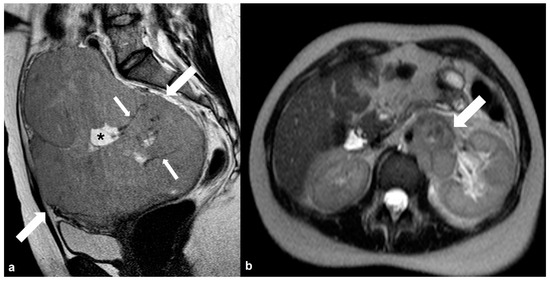

2.4.3. Dysgerminoma

2.5. Pregnancy